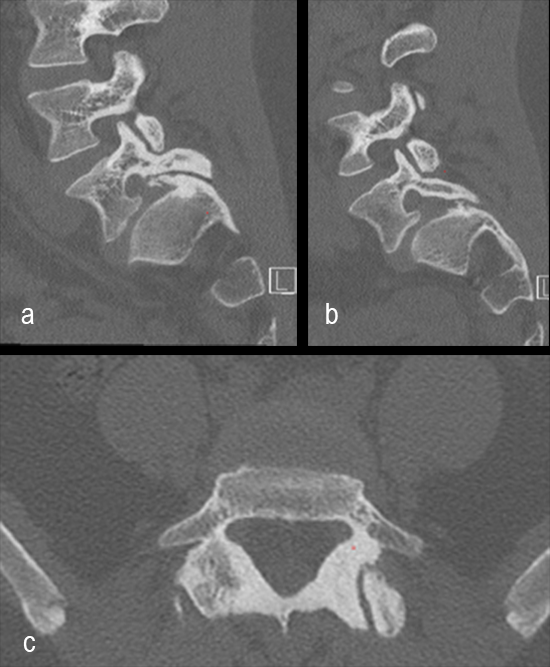

A 17-year-old girl presented to the spine clinic with significant low back pain. X-ray, CT and MRI imaging (Figs 1-3) showed evidence of spondylolisthesis. Upon clinical examination of spinal alignment, the patient was found to have a pelvic incidence of 78°, a lumbar lordosis of 54°, and a pelvic tilt of 51°.